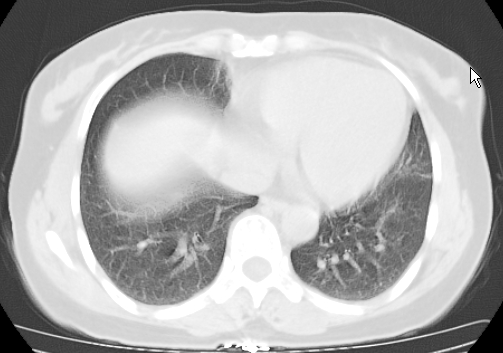

标题: CT25227:背部疼痛伴双侧胸壁痛2月,食欲差。 [打印本页]

标题: CT25227:背部疼痛伴双侧胸壁痛2月,食欲差。

肺结核并胸椎结核?请各位高手指教。

用椎体的条件来扫胸椎呀!考虑1左侧胸膜小结节形成2椎体结核并冷脓肿形成

考虑胸椎结核并椎旁软组织肿胀。

左肺结核灶,胸椎结核并冷脓肿。

左肺结核灶,胸椎结核并冷脓肿